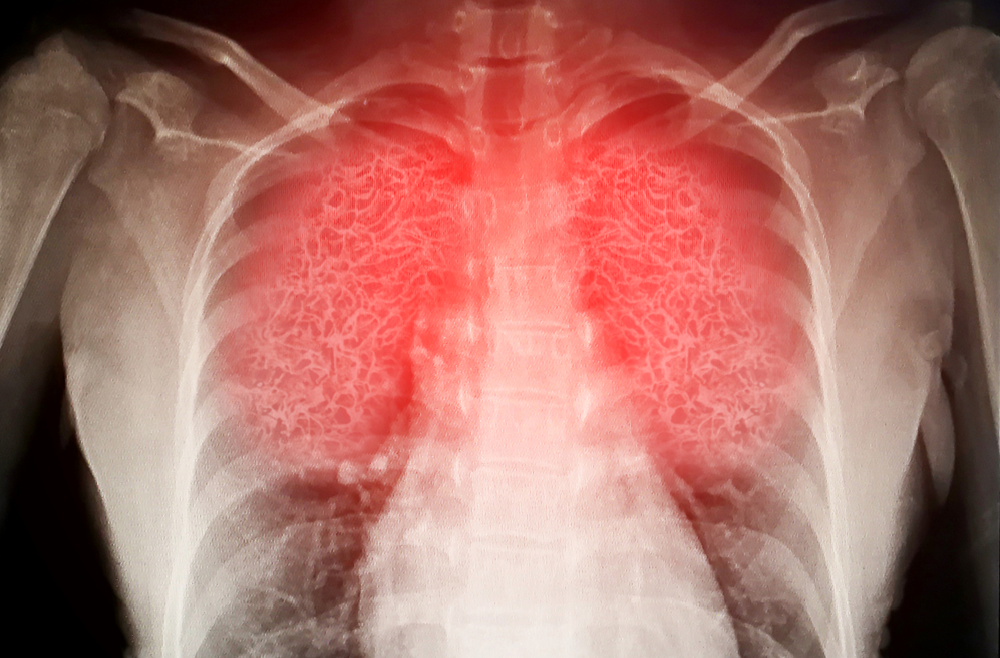

3歲的庭庭日前因有咳嗽、流鼻水且持續高燒2天的症狀,醫師給予症狀治療藥物後便讓其返家觀察。但6天後仍舊高燒不退,咳嗽也愈發嚴重,甚至出現嘔吐、腹痛等情況而前往醫院急診,經X光檢查,發現其左肺出現嚴重肺炎,透過核酸檢測確診為感染「人類間質肺炎病毒」,又抽血檢查顯示其白血球高達23,000u/L(正常值為4,000-10,000u/L),發炎指數更是上升至18.2mg/dl(正常值小於1mg/dl),安排尿液肺炎鏈球菌抗原檢測發現庭庭還合併肺炎鏈球菌感染,收治入院。

此種病毒好發於2至3歲以下的幼童,具有氣喘、肺部疾病史與免疫系統較弱者容易使其症狀更加嚴重。春末夏初的季節可能出現流行期,診斷方式可透過抗原篩檢與核酸檢測來確認,如果懷疑進展為肺炎就需要進一步影像學檢查。